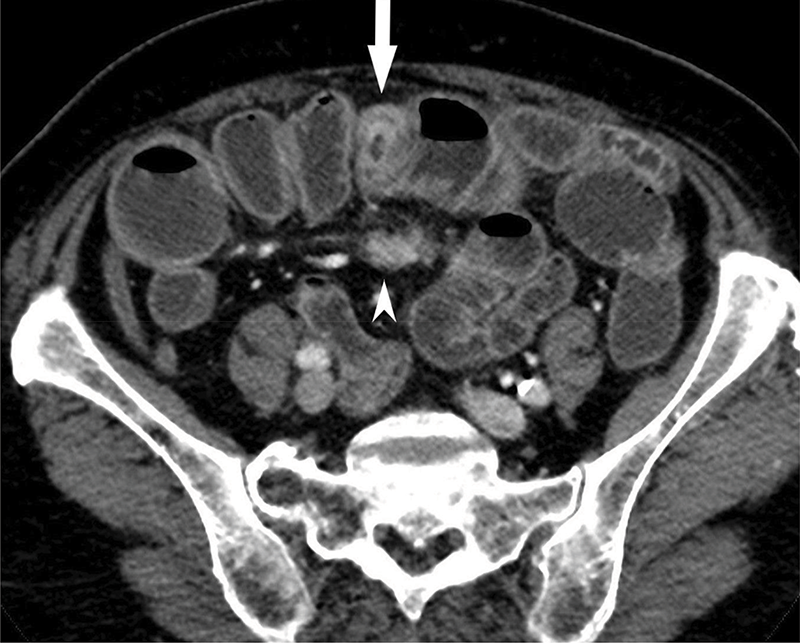

Figure 1a

CT showing contrast‑enhancing ileal NET (arrow) and mesenteric mass (arrowhead).